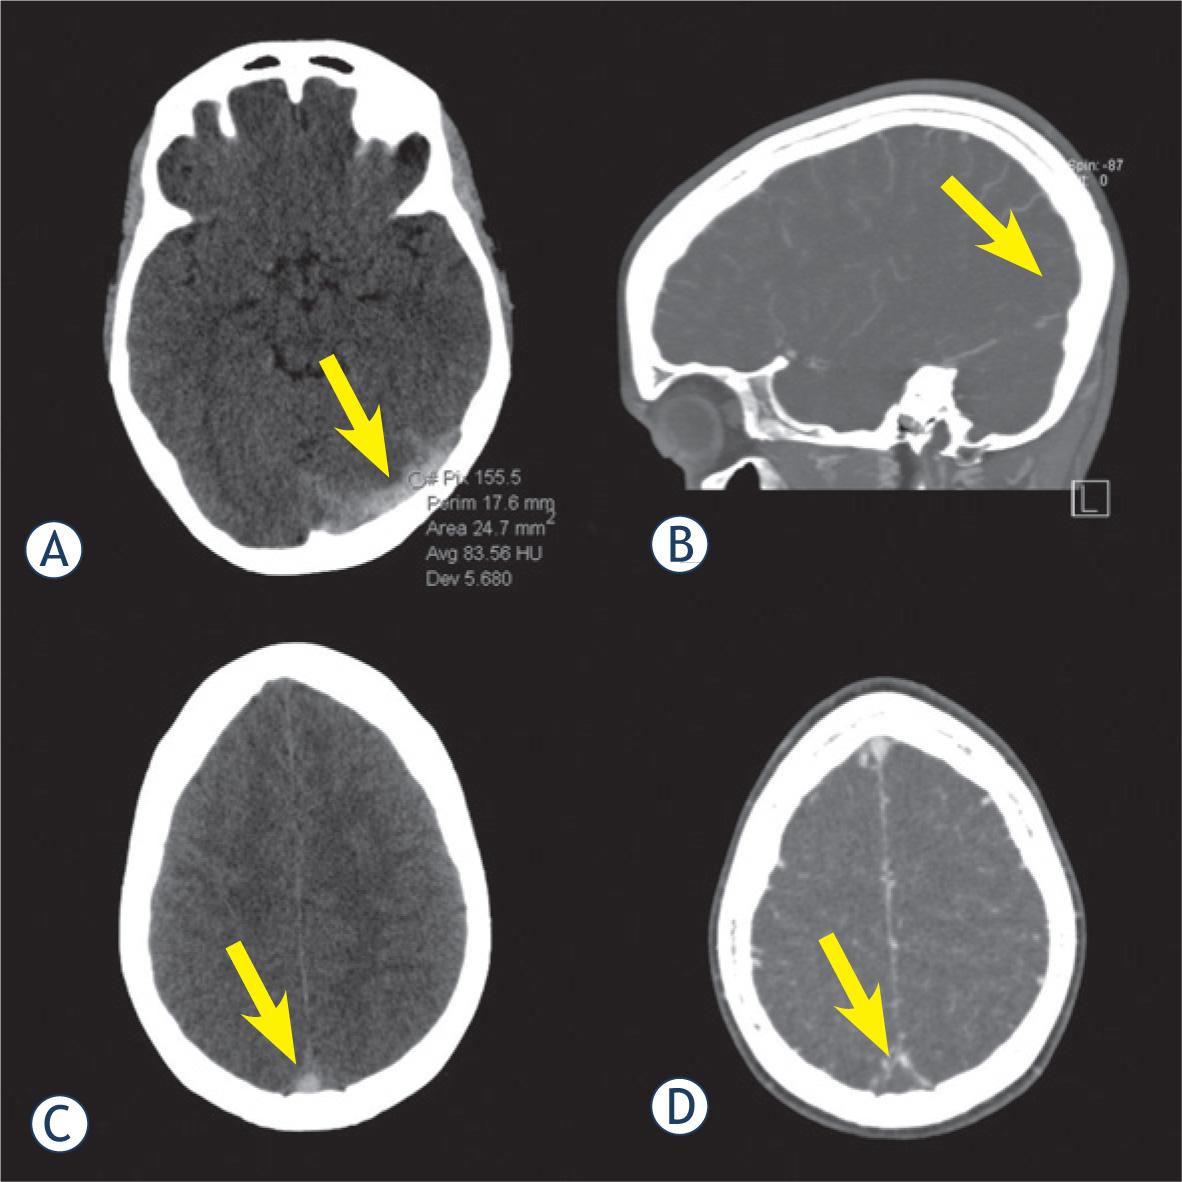

Transverse sinus was the most commonly thrombosed structure, followed by sigmoid sinus (Table 1). Typical NCCT findings of CVST are depicted in Figure 1. All 13 patients with CVST were accurately diagnosed by both observers. Therefore, the calculated sensitivity was 100% in both readings, with specificity of 80 and 87.5%, respectively. Kappa value regarding the presence or absence of thrombosis was 0.72, which is considered to represent a good agreement between observers. Sensitivity and specificity of NCCT for overall presence of thrombosis were 100% and 83%. Average diagnostic confidence level regarding the presence or absence of CVST was 2.1 ± 1.2 (very certain). A case with false positive finding is depicted in Figure 2.

19-year-old female with thrombosis (arrow) of the left transverse sinus (LTS) (A) and superior sagittal sinus (C), confirmed by CT venography in sagittal (B) and axial (D) reconstruction. Average attenuation inside the LTS was 83.6 HU.